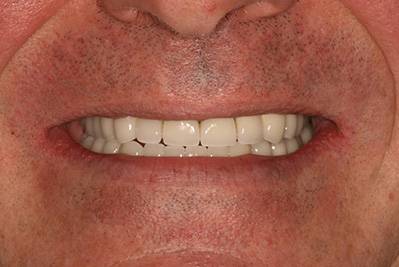

6. Eset

Nagymértékű fogkopás, erózió, csikorgatás a teljes rágóapparátust túlterhelve okoz reménytelennek tűnő helyzeteket.

Ebben az esetben implantátumok , koronák és hidak segítségével változtattunk a páciens fogainak érintkezésén. 6 hónapig ideiglenes hidakkal teszteltük a megváltoztatott harapási pozíciót. Ezután készültek el a végleges fix pótlások.